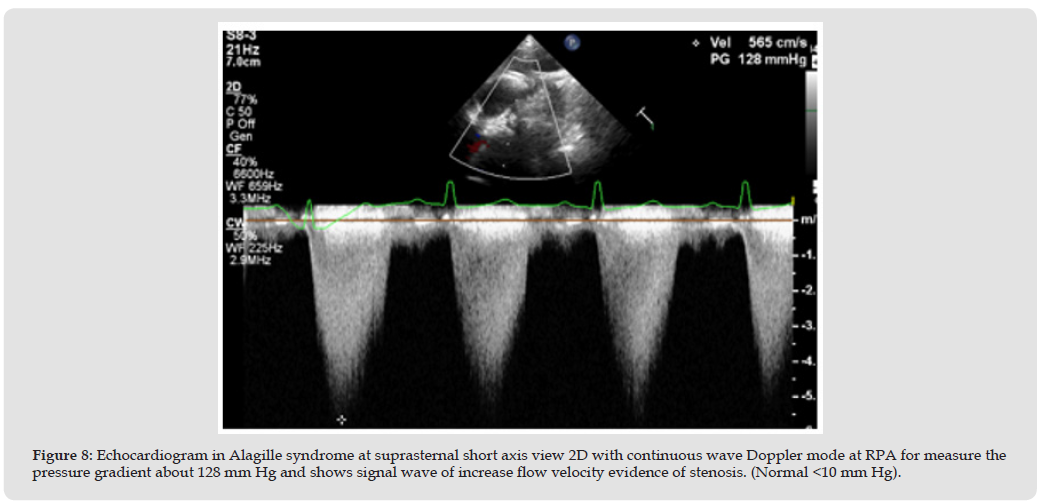

In patients with hepatomegaly, the apical 4 chambers angle is easier to perform and provides a clearer echocardiography image (Figures 1 & 2). This is because of two reasons:

1. These children are usually underweight, and have thin chest walls, which makes it not difficult to examine the apical area. The transducer can send ultrasound waves to the heart.

2. In hepatomegaly case, the liver pushes the heart 1-2 intercostal spaces higher than normal, which pushes the apex closer to the wall too [3] Although CT or MRI are the standard equipment for demonstrating pulmonary branch structure in long segment.